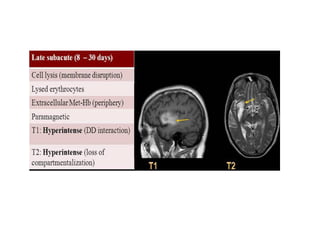

d) Late Subacute Infarct (5 days-2 weeks) :

-The subacute phase is characterized by resolution of

vasogenic edema and reduction in mass effect

-A key imaging finding is gyriform enhancement which

may occasionally be confused for a neoplasm , unlike

a tumor , subacute infarction will not typically show

both mass effect and enhancement simultaneously ,

enhancement be seen from approximately 6 days to

6 weeks after the initial infarct

-Diffusion may remain bright due to T2 shine through ,

although ADC map will either return to normal or

show increased diffusivity